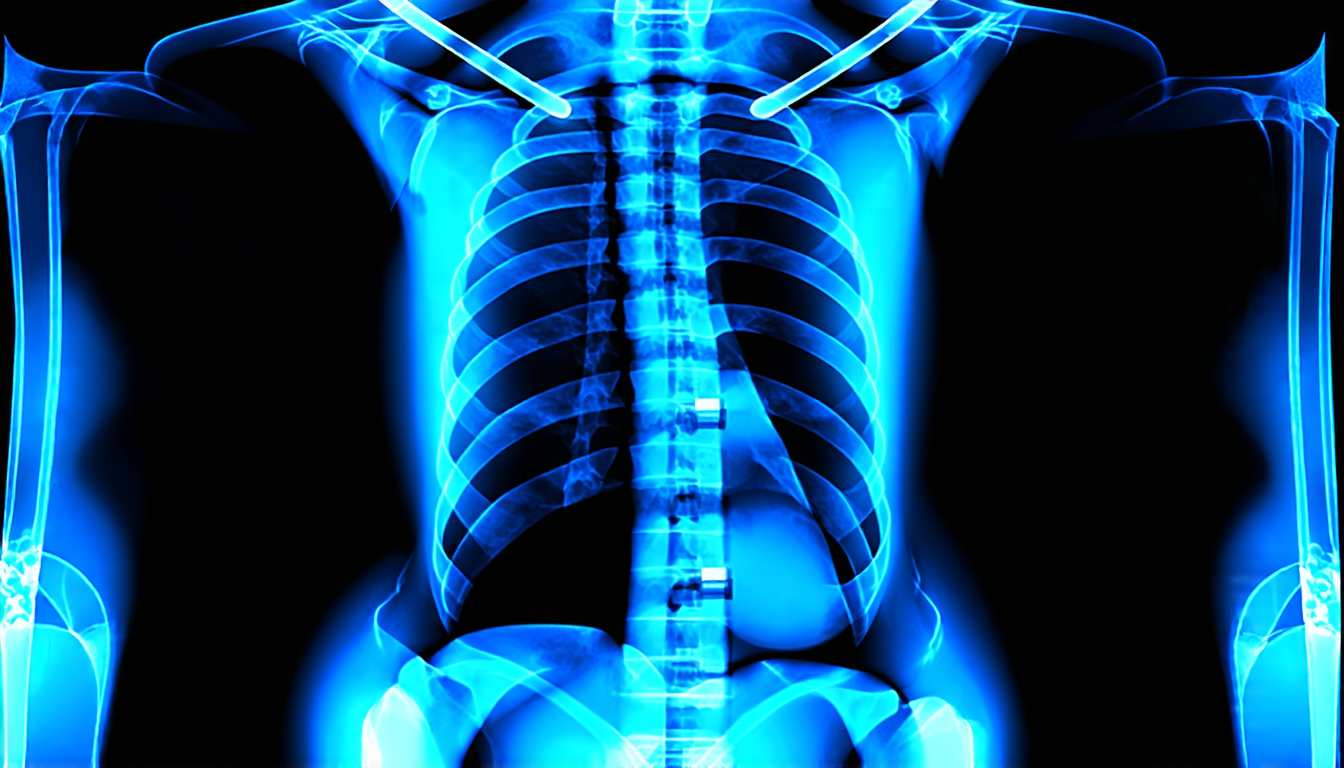

To address this issue, researchers have proposed a novel approach for generating synthetic data for instance segmentation tasks. The method involves inserting arbitrary shapes into chest X-ray images, guided by anatomical structures, to create realistic foreign object scenarios. This allows for the creation of large datasets with minimal manual annotation effort.

The team behind the project used a combination of structure plotting and cut-and-paste augmentations to generate synthetic data. They inserted various shapes, such as lines, polygons, and ellipses, into anatomical regions, mimicking real-world foreign objects like stents, pacemakers, and surgical clips. The generated images were then annotated with pixel-wise masks for further instance segmentation purposes.